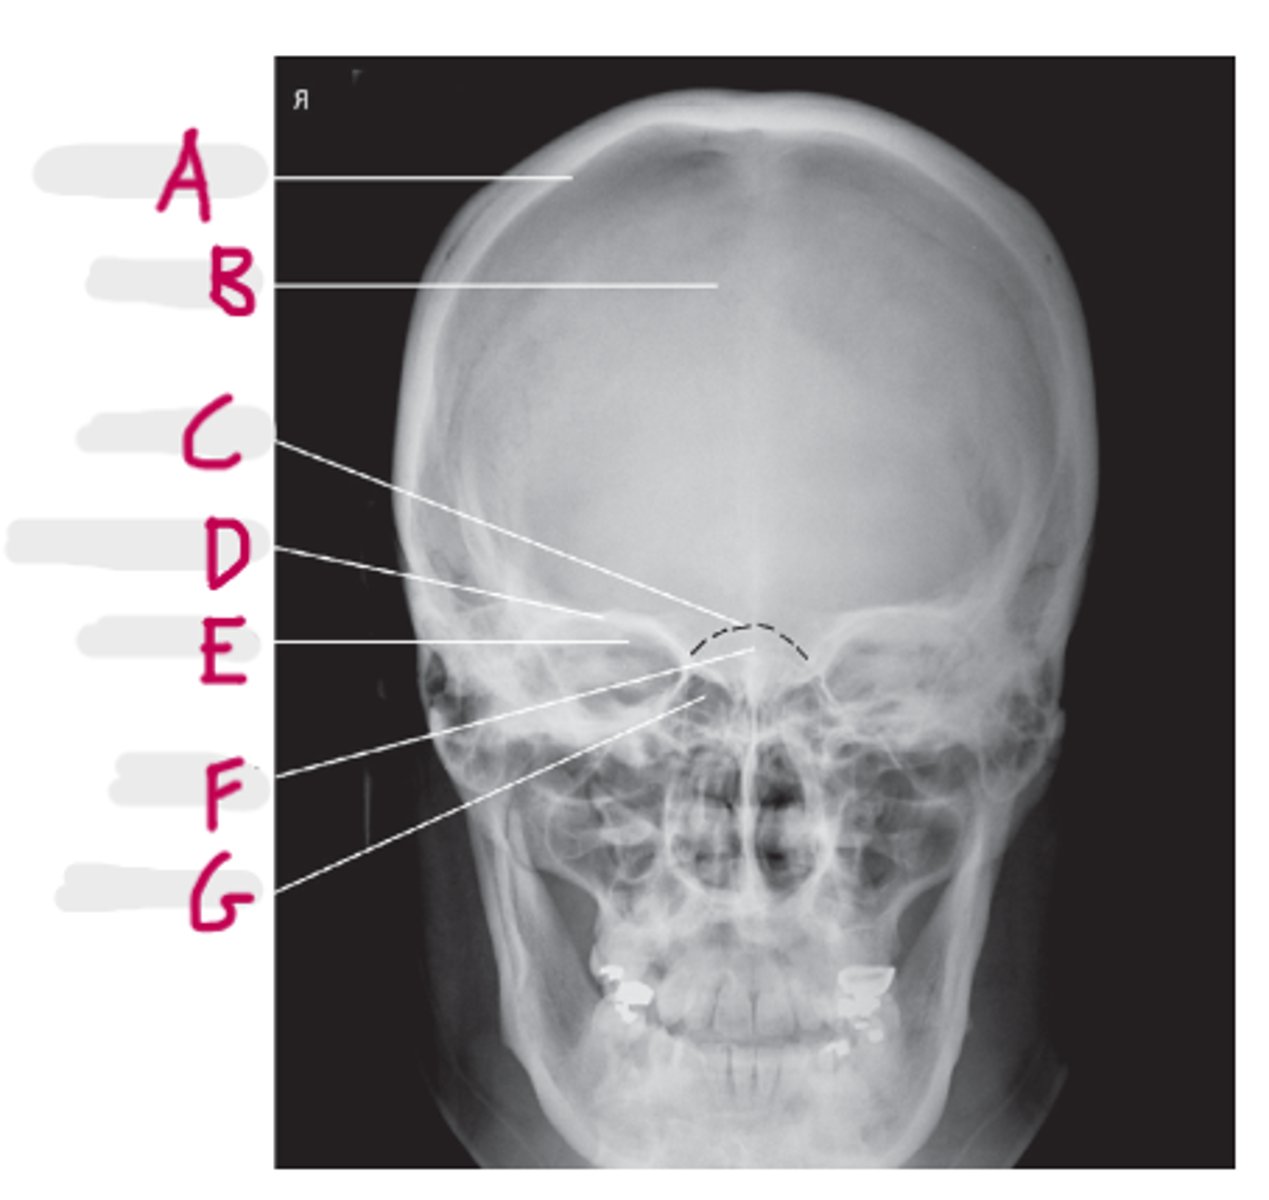

Frontal sinus

A

Crista galli

B

Superior orbital margin

C

Superior orbital fissure

D

Ethmoid sinus

E

Petrous ridge

F